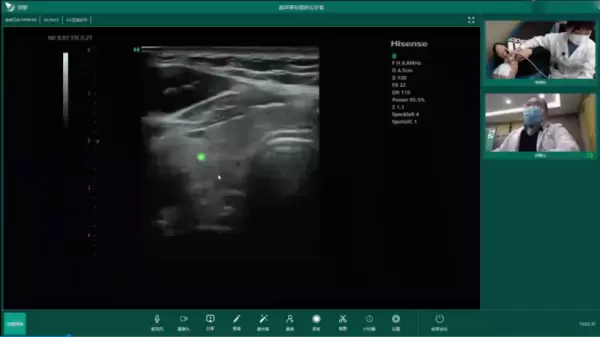

“局部放大看一下我圈出来的这个结节,取它的最大切面冻结、测量一下。”2月22日下午,青岛大学附属医院超声科副主任医师郑曙光博士在医院远程超声会诊室,通过大屏幕对300公里之外的平邑县柏林镇卫生院高斌医生进行远程会诊指导,这样的会诊指导场景双方已经开展了近2年时间。

在大屏幕上,基层医院检查室画面与超声图像实时显示,线上语音和创新的激光指针配合指导让郑博士如同现场实操。不到5分钟,在郑博士的指导下,双方完成了一例甲状腺结节病例的远程会诊。

为助力基层医疗体系建设,2021年3月海信医疗为双方搭建远程超声会诊系统,实现基层超声首诊、三甲医院会诊的远程诊断模式,通过优质医疗资源下沉,让基层患者足不出户就能享受到三甲医院的诊疗服务。海信医疗创新研发的激光指针技术让远程会诊更加精准、高效。

现在,每次进行远程会诊时,郑博士都会第一时间打开激光指针,屏幕实时传输指针位置,通过语音和操作对基层医生进行指导。“激光指针很实用,用指针圈在病灶位置上,基层医生能同步看到,一目了然,缩短了我们的沟通时间。”郑博士使用后评价。